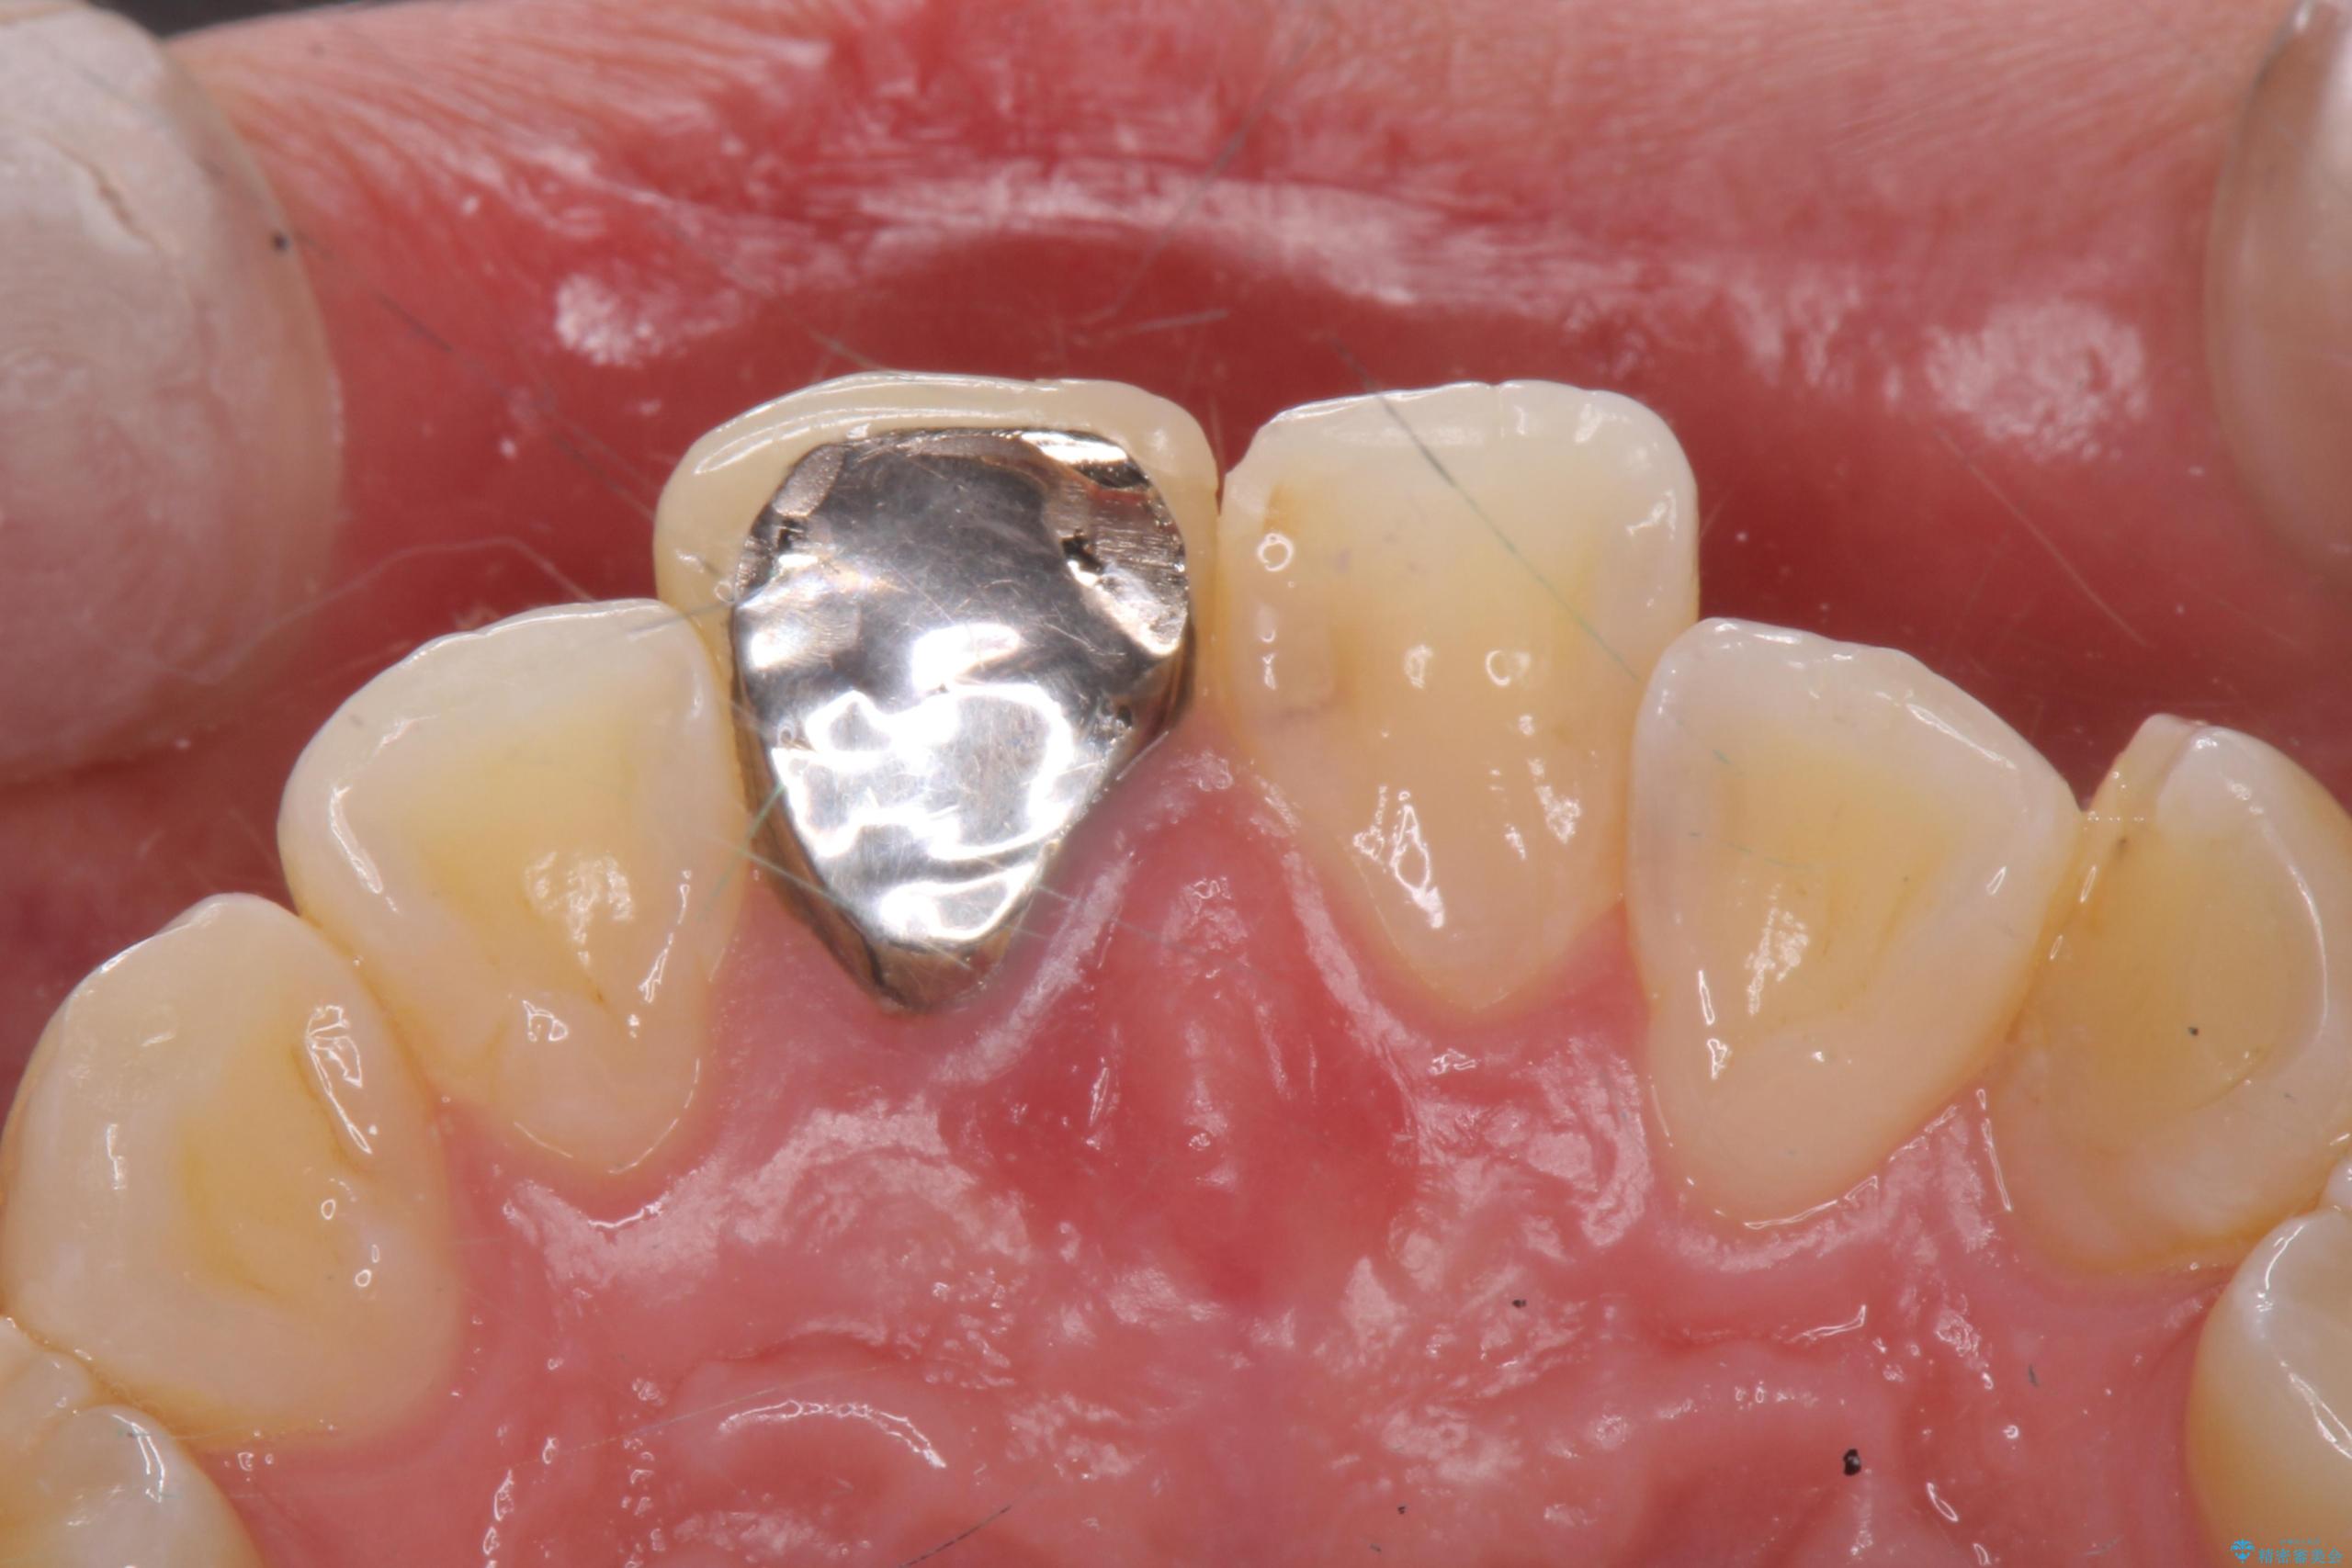

- 前歯のかぶせ物の色が気になるとのことで来院された患者様です。

セラミッククラウンで作り変えていきます。

- 右上1: 仮歯/11,000円、ジルコニアクラウン(スタンダード)/121,000円 合計132,000円(税込)費用は治療当時の料金となります